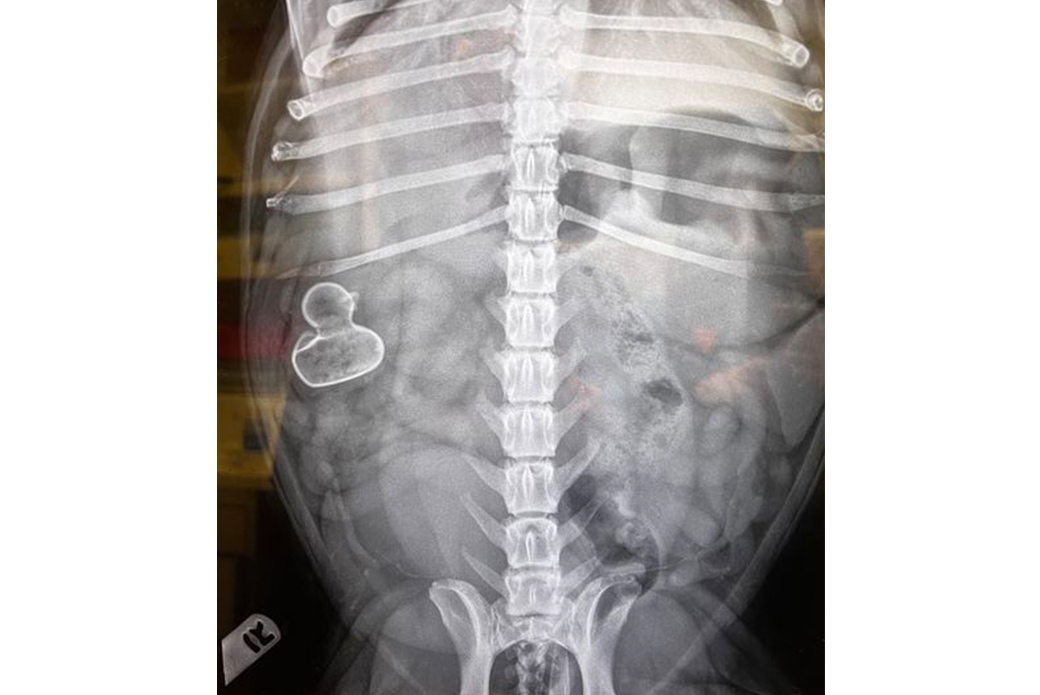

The team performed an X-ray of Apo’s abdomen, and the results were unmistakable: A rubber duck was lodged in Apo’s small intestine.

“Sometimes in cases of foreign body obstructions, we have no idea what we're going to find until we get in there,” says Dr. Relman. “In Apo’s case, the X-rays were so definitive, and the shape so recognizable.

Apo immediately went into surgery, where Dr. Julie DiMeglio and Carol Algarin, a Licensed Veterinary Technician, found the rubber duck stuck in Apo’s duodenum—small intestine—just past his stomach. Dr. DiMeglio cut into a healthy part of the duodenum where the toy hadn't yet reached and pushed it out through the opening. Then she closed the hole.

“It may seem funny now, but this was a nightmare,” says Oscar, who framed a copy of Apo’s X-ray.

“A rubber duckie swallowed whole—an X-ray for the books, for sure,” says Dr. Maren Krafchik, the hospital’s Director of Medical Operations.